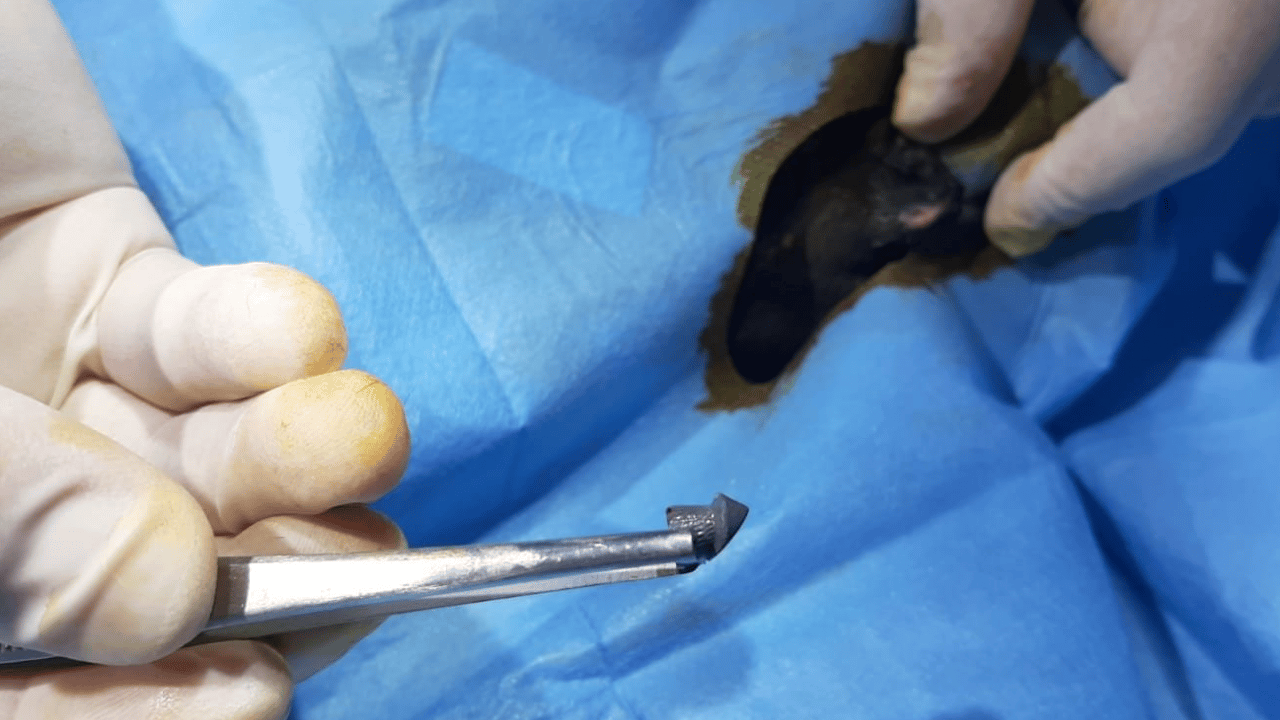

KOMŞUSUNDAN ŞİKAYETÇİ OLDU Hüseyin Bülbül, komşusu K.G.'den şikayetçi oldu. Eve giden İpsala İlçe Emniyet Müdürlüğü ekipleri, K.G.'ye ait ruhsatlı 2 av tüfeğine incelenmek üzere el koydu. Öte yandan K.G.'den alınan svap örneklerinde sol elinde atış artıklarına rastlandı. K.G., emniyetteki işlemlerinin ardından adliyeye sevk edildi. Savcılık ifadesinde suçlamaları kabul etmeyen K.G., yurt dışına çıkış yasağı konularak adli kontrol şartıyla serbest bırakıldı. 'YETERLİ ŞÜPHE OLUŞTURACAK DELİL MEVCUT' İpsala Cumhuriyet Başsavcılığı'nın olaya ilişkin hazırladığı iddianamede K.G., hakkında, 'Bir ev hayvanını veya evcil hayvanı kasten öldürme' suçundan 6 aydan 3 yıla kadar hapis cezası istendi. İddianamede, "Herhangi bir silah ateşleme görüntüsü tespit edilmese de şüphelinin ikamet ettiği evin bahçe kapısı önünde bir kedinin can çekiştiği ve bir kedinin de kaçtığının tespit edildiği, dosya kapsamında tanık olarak beyanı alınan S.Ç.'nin şüphelinin bahçe kapısı önünde bir kediyi yatar vaziyette gördüğünü, başını sevmek istediğinde kedinin ölü olduğunu fark ettiğini, kediyi eline aldığında başından kan aktığını görmesi üzerine yol üzerinde kalmaması amacıyla kediyi çöp tenekesinin içerisine bıraktığını, ölen ve yaralanan 2 kedi hakkında düzenlenen 25/08/2025 tarihli veteriner hekim ön muayene raporu ile çekilen radyografilerde ateşli silah yaralanması (kuş saçması) ile uyumlu patolojiler gözlemlendiği şeklinde rapor tanzim edildi. Tüm dosya kapsamı incelenmekle şüpheli savunması, bilgi sahibi beyanları, İpsala İlçe Tarım Müdürlüğü'nün yazılı başvurusu, müşteki beyanı, kamera görüntüleri ve kriminal raporları birlikte değerlendirildiğinde, şüphelinin olay tarihinde müşteki Hüseyin Bülbül tarafından da beslenmekte olan sokak kedilerine ateş etmek suretiyle, bir kedinin ölümüne neden olarak üzerine atılı suçu işlediğine dair ve bir kedinin yaralanmasına neden olarak tariflenen suçu işlediğine dair hakkında kamu davası açmak üzere yeterli şüphe oluşturacak kadar delilin mevcut olduğu anlaşılmakla" denildi.

SUÇLAMALARI KABUL ETMEDİ Sanık K.G.'nin yargılanmasına İpsala 2'nci Asliye Ceza Mahkemesi'nde başlandı. Tutuksuz yargılanan sanık K.G., hakkındaki iddiaları kabul etmeyerek, masum olduğunu söyledi. K.G., hakkında adli kontrol kararının devam etmesine karar verilerek duruşma ertelendi. 'İLK CELSEDE DELİLLER TOPLANDI' Hüseyin Bülbül'ün avukatı Edirne Barosu Keşan Temsilcisi ve Hayvan Hakları Komisyonu Başkanı Büşra Ağır Ürkmez, kedilerin 2018 yılından bu yana sistematik olarak öldürüldüğünü belirterek, "En somut adımlar, 24 Ağustos 2025 tarihiyle Hüseyin Bülbül'ün şikayet etmesi neticesinde başlamıştır. Davanın ilk celsesi görüldü. İlk celsede deliller toplandı. Balistik rapor sonucu dosyaya ibraz edilmiştir. Şüpheli beyanlarında suçu işlemediğini, bu olayla ilgi ve alakasının olmadığını söylemişse de dosyadaki mevcut deliller, tanık beyanları şüphelinin ifadelerinin gerçeği yansıtmadığını ortaya çıkarmaktadır. Bu konuyla ilgili olarak davanın takipçisi olacağız" dedi. 'KONUNUN TAKİPÇİYİZ' K.G.'nin kedileri bahçesinde ateşli silah ile vurduğunu belirten Ürkmez, "Bununla ilgili delillerimizi dosyayla sunmuş bulunmaktayız. Onun haricinde veteriner ön raporunda da kedilerin ölümüyle ilgili olarak vücutlarında saçma bulunduğu açıklığa kavuşmuştur. Kamera kayıtlarımızı da delil olarak dosyayla sunduk. Bu konunun takipçisiyiz. '5199 sayılı Hayvan Haklarını Koruma Kanunu gereği de şüphelinin ceza alması için elimizden gelen her şeyi baro olarak yapmak niyetindeyiz. Bununla ilgili son kararı mahkeme verecektir. Şüphelinin yurt dışına çıkış yasağı ve adli kontrolü ise devam etmektedir" diye konuştu. Hüseyin Bülbül ise davanın sonuna kadar takipçisi olacaklarını kaydederek, K.G.'nin hak ettiği cezayı almasını istediklerini söyledi.